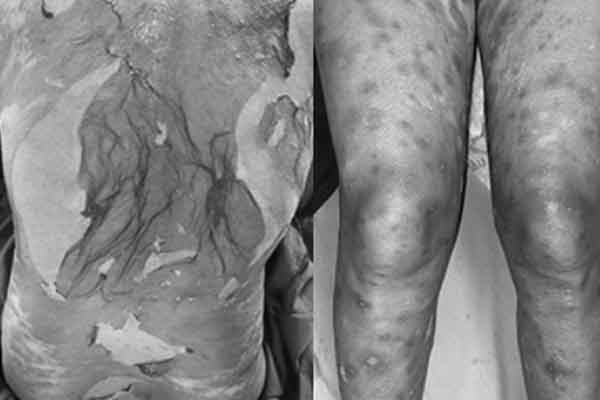

Trẻ nhập viện với các vết lở loét kín cơ thể. Ảnh: BVCC.

Tại Bệnh viện Nhi đồng Thành phố (TP.HCM), bệnh nhi đã loét sưng nề tiến triển các lỗ tự nhiên cơ thể (môi, mũi, hốc tai, vùng kín, hõm nách, bẹn…). Em thở mệt và nhiễm trùng da, nhiễm trùng huyết toàn thân nên được hỗ trợ thở máy, kháng sinh, Immunoglobulin tiêm truyền và chăm sóc vô trùng tuyệt đối.

Trẻ phải ăn qua ống sonde dạ dày do môi miệng bị loét nặng không thể ăn bình thường. Việc vệ sinh rất khó khăn, trẻ ngứa và đau, thị lực giảm. Các bác sĩ hội chẩn các chuyên khoa mắt, niệu, da liễu, chỉnh hình, phục hồi chức năng. Các y bác sĩ Khoa Hồi sức tích cực - Chống độc từng bước khống chế nhiễm trùng, đã có da non, cải thiện dần các giác quan cho trẻ.